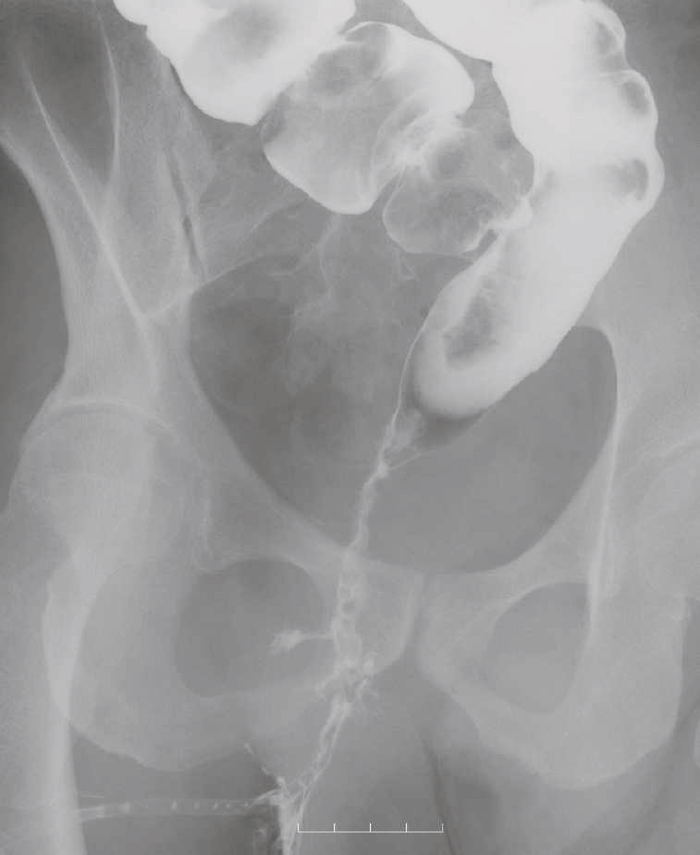

図42 注腸造影検査

注腸造影検査では,直腸は狭小化しており,痔瘻に続く,瘻管が描出された。

図43 腹部骨盤CT

CTではMRIと同様に広範囲のhigh density areaがあり,癌と炎症が波及した領域の区別がつかず右側方領域にリンパ節腫大を認めた。